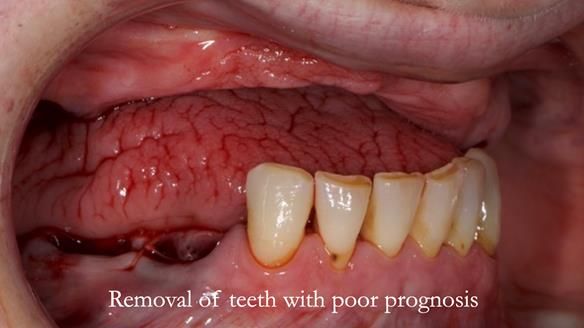

- The upper natural teeth have hopeless prognosis due to dental caries.

- The LR6, 5, 4 have guarded prognosis because of dental caries.

- The lower front teeth (LR3 – LL3) have better prognosis (although, I think there is high chance of loss – over the next 10 - 15 years). However, I do not believe it is right to remove them as they are in good condition compared with the other teeth and coping with a lower full denture is far more difficult (affecting your quality of life) than a lower metal based partial denture supported by natural teeth as proposed in the treatment plan below.

- Upper complete denture and lower partial denture along with removal of failing teeth - Jo wanted this

The clinical situation and treatment process is shown in detail below. I provided the clinical work. Rowan Garstang provided the technical work. This treatment took 25 visits over a period of 12 months.